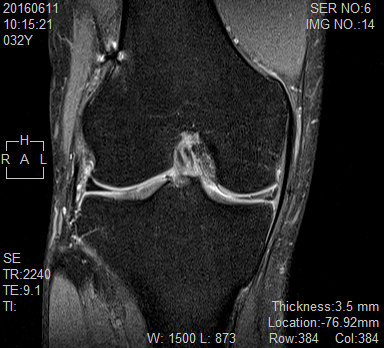

診察室で先生と一緒に見たのは、膝の断面が映ったMRI画像でした。太ももの骨とすねの骨のあいだに、三角形の組織が映っています。先生の説明によると、それが半月板とのことでした。

向かって右側の半月板の一部に、前回の手術で縫合したと思われるラインがあり、さらにその少し内側に新しい亀裂のような影が見えると教えてもらいました。専門的なことは正直よくわかりませんが、「前回とは別のところにも傷が入っている可能性が高い」という説明を受けたとき、胸のあたりがずしんと重くなったのを覚えています。